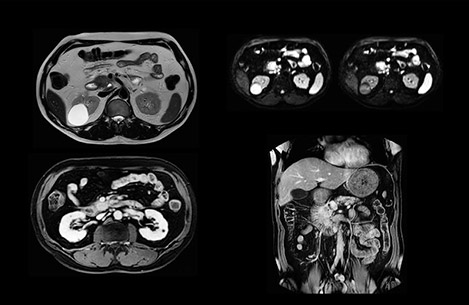

“Our liver exams are quite fast,” says Dr. Baumann. “If the patient tolerates it, we use an arms-up position to reduce the FOV and speed up the exam with dS SENSE.” “We acquire one transversal high resolution T2-weighted sequence with 3 mm slice thickness, for example for pancreas or liver lesions. Then we also add a T2 fat suppressed MultiVane XD SPIR sequence. We perform these two routinely in our liver imaging. We use high dS SENSE factors to significantly shorten scan times to 2-4 minutes, which can improve our protocol; it’s a very robust scan.” “We include mDIXON for the dynamic sequences because of the robust and homogeneous fat suppression we get with that. We had been using eTHRIVE, but we are now quite happy with mDIXON. Sometimes we use a medication to calm the bowels, to further improve the image quality.”

“We are more confident in our diagnosis if we don’t have to rescan the patient and compare it to other studies; this liver exam gives us good image quality in a faster time than the default system’s approach with arms down. That makes a difference for the patients, too. The shorter scan times, especially with the high dS SENSE factors, shorten the duration of the total examination. At the same time it’s more comfortable for the patient, to rest normally without holding the breath, just relaxing.”